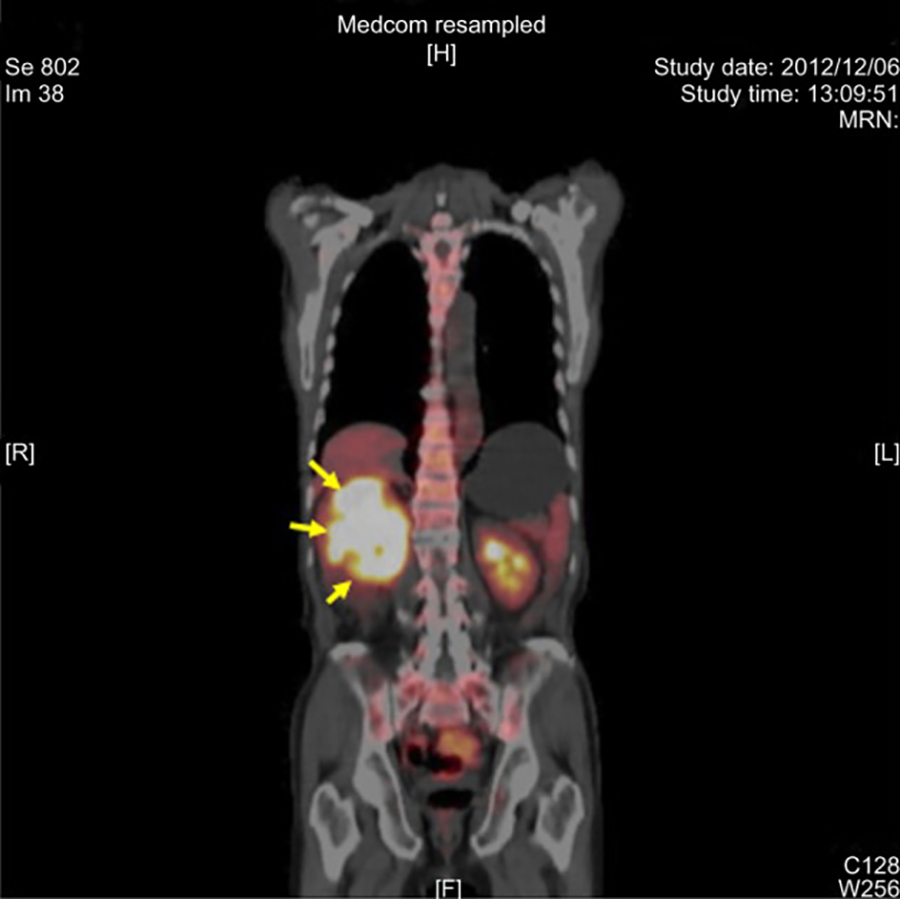

![Value of [68Ga]Ga-NYM046 PET/CT, in Comparison with 18F-FDG PET/CT, for ...](https://jnm.snmjournals.org/content/jnumed/65/12/1884/F5.large.jpg)